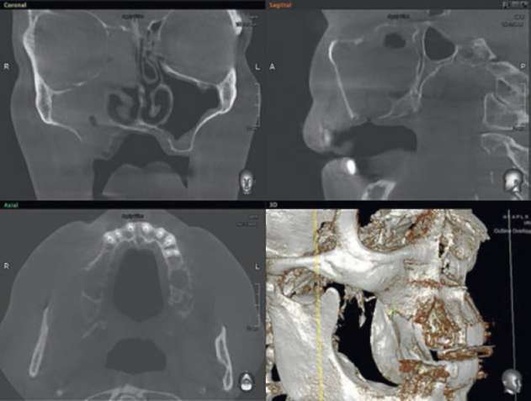

Адекватное хирургическое вмешательство и послеоперационное лечение способствуют выздоровлению. В некоторых случаях возможно самопроизвольное закрытие перфорации. Врачебная ошибка при обнаружении перфорации во время удаления зуба или вовремя нераспознанная перфорация могут привести к развитию острого перфоративного синусита. Пациенты нередко обращаются спустя несколько дней после удаления зуба с жалобами на выделения из лунки, попадание жидкости из полости рта в нос и воздуха из полости носа в рот. У львиной доли пациентов с перфорацией верхнечелюстной пазухи на основании КЛКТ были зарегистрированы деструктивные процессы в области нижней стенки ВС. Важным диагностическим этапом является проведение радиологического исследования, но вместе с тем следует указать, что проведение панорамной радиографии челюстей, черепа в аксиальной и других проекциях, зонограмм и радиологических исследований с применением контрастирующих средств на современном этапе не обоснованно в связи с низкой информативностью данных исследований. Эффекты суммации, нередко низкое качество получаемого изображения, плоскостные искажения не позволяют врачу проводить диагностику прецизионно, а учитывая уровень лучевой нагрузки, получаемый пациентом на рентгенологических аппаратах старых образцов, становится очевидно, что КЛКТ можно назвать «золотым стандартом» обследования пациентов с патологиями придаточных пазух носа (рис. 5.84, 5.85).

image

Рис. 5.84. Компьютерная томограмма до начала терапии острого одонтогенного верхнечелюстного синусита

Рис. 5.85. Компьютерная томограмма после окончания консервативной терапии

На компьютерных томограммах диагноз «острый ВС» может выглядеть очень разнообразно, но вместе с этим всегда имеются четкие диагностические критерии - наличие одонтогенной причины (инородное тело, перфорация, признаки эндоантрального синдрома), «наличие пузырьков воздуха» и признаки обструкции естественного соустья ВС.